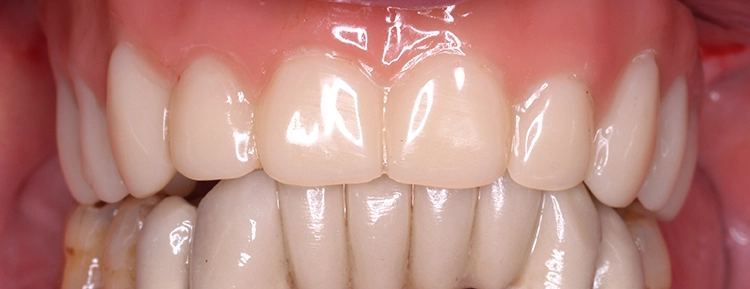

Der Patient wurde am gleichen Tag mit dem festsitzenden Brückenprovisorium entlassen und ausführlich über die Mundhygiene des Langzeitprovisoriums postoperativ aufgeklärt. Abbildung 8 zeigt eine regelrechte Implantatposition in der postoperativen Panoramaschichtaufnahme. In Abbildung 9 ist die postoperative Versorgung in situ zu sehen.

Der Patient erhielt eine engmaschige Nachsorge, um biologische Komplikationen, rechtzeitig zu erkennen. Im Verlauf zeigte sich eine regelrechte Wundheilung und Implantateinheilung sowie eine erhebliche Steigerung der mundgesundheitsbezogenen Lebensqualität des Patienten durch den gaumenfreien Zahnersatz.